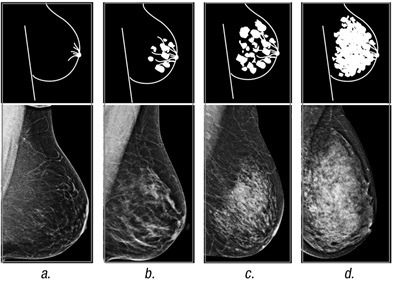

Nondense breast tissue appears dark and transparent on a mammogram. In contrast, dense breast tissue appears as a solid white area, which makes it difficult to see through.

The radiologist who analyzes your mammogram determines the ratio of nondense tissue to dense tissue and assigns a level of breast density. The levels of density are described using a results reporting system called the Breast Imaging Reporting and Data System, which is provided by the American College of Radiology.

The levels of density are often recorded in your mammogram report using letters:

- A — This level indicates that the breasts are almost entirely composed of fat. About 1 in 10 women has this result.

- B — Scattered areas of fibroglandular density indicate there are some areas of density, but most breast tissue is nondense. About 4 in 10 women have this result.

- C — Heterogeneously dense indicates some areas of nondense tissue, but most breast tissue is dense. About 4 in 10 women have this result.

- D — Extremely dense indicates that nearly all breast tissue is dense. About 1 in 10 women has this result.

In general, women with breasts that are classified as heterogeneously dense or extremely dense ― levels C and D ― are considered to have dense breasts. About half of women undergoing mammograms have dense breasts.